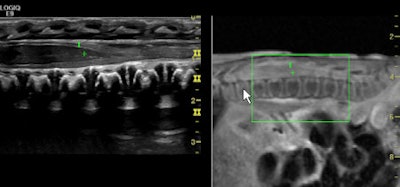

As the use of musculoskeletal ultrasound accelerates, due in part to the wider availability of handheld and portable units and the growth of image fusion, European specialists led by Dr. Andrea Klauser have developed new guidelines to inform physicians and sonographers about its appropriate clinical applications.

Evidence-based guidelines reflecting a consensus of best-practice opinion by a group of 16 experts in this specialty appear in the May issue of European Radiology. Hundreds of articles published in peer-reviewed journals were scrutinized over a two-year period to produce clinical guidelines for the six anatomical areas where musculoskeletal ultrasound is commonly employed. These include the shoulder, elbow, wrist, hip, knee and ankle/foot (Eur Radiol, 2012, Vol. 22:5, pp. 1140-1148).